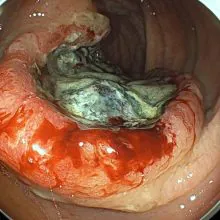

- 進行大腸がん